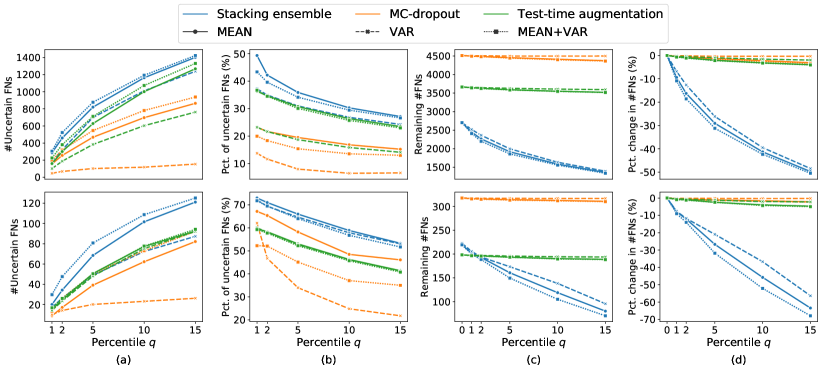

5.1 Distribution of Uncertainty Scores

Distribution of Uncertainty Scores Across Different Severity Levels As explained in Section 3, each uncertainty metric essentially defines an order/ranking among the data points. We conducted an analysis to better understand what data will be assigned high uncertainty under a particular uncertainty metric . Picking out the highest ranked data points (), we calculated the ratio of data points from each SL. Figure 4 summarizes the results as box plots for the Kaggle-DR and the Messidor-2 datasets; additional detailed statistics can be found in Table S.1 in the supplementary materials. From the plot and table, SL1 & SL2 examples account for a higher proportion among the top-ranked uncertain examples across the three ensemble methods. This finding matches our intuition that incipient disease examples (SL1 & SL2) are more likely to be considered uncertain by ensemble methods due to their ambiguity.

Comparing the three ensemble methods in Figure 4, the stacking ensemble method has the highest ratios of SL1 & SL2 data among the high-uncertainty examples it identified under both mean and var. TTA showed slightly better performance than MC-dropout but still falls behind the stacking ensemble method. Considering the fact that SL0 examples accounted for the majority of the dataset, the stacking ensemble method was much more precise (specific) in selecting truly ambiguous data points that were difficult to classify. From Figure 3, we can also see that the stacking ensemble method greatly outperformed the other two methods in finding false negatives under both mean and var uncertainty metrics.

In contrast, the MC-dropout method showed the worst overall performance among the three, as it can be seen from the high ratios of SL0 examples among the uncertain negatives in Figure 4. The histograms in Figure 2 provides another perspective to look into the phenomenon, where a decent proportion of MC-dropout model’s predictions on SL0 inputs entailed low confidence (far from 0 or 1), which from another angle explained why MC-dropout was less specific in terms of lower FNP; many no-DR inputs (i.e. SL0) were erroneously assigned high uncertainty by MC-dropout models.

It is still an open question why the evaluated MC-dropout networks signaled relatively high uncertainty on SL0 & SL3 & SL4 data that are less likely to be ambiguous. We conjecture that much of the “uncertainty” indicated by disagreement among test-time dropout samples actually reflects the stochastic nature of dropout networks rather than the real decision uncertainty associated with the data. It is worth noting that the MC-dropout model we evaluated was not weak per se; they all achieved above Area Under Curve (AUC) scores on test sets. The weakness of individual test-time samples (which explains their low-confidence predictions on SL0 & SL3 & SL4) might have been hidden when they are aggregated into an ensemble—a well-known advantage of ensemble learning. Our results suggested that the uncertainty information given by implicit ensemble methods such as MC-dropout and TTA might not be as reliable as that from explicit ensemble approaches (e.g., stacking ensembles). Similar findings on MC-dropout can be found in some previous papers [1].